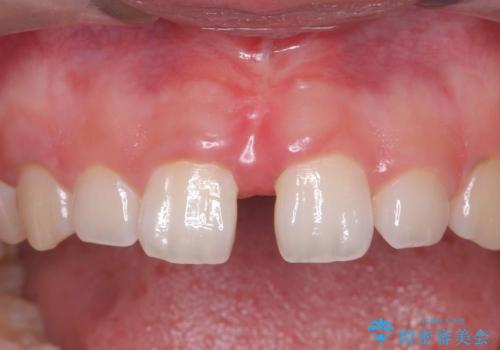

【上唇小帯切除術】子どもの頃から上の前歯の歯茎が気になってた!

担当医 河野豊嘉